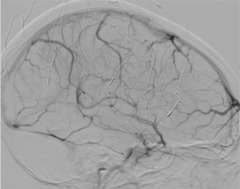

Sinus Thrombosis Figure 1: Normal

Figure 1: Normal

Cerebral venous sinus thrombosis is a rare condition when a large blood clot forms in a large vein in the brain called a dural venous sinus. The clot blocks the dural sinus and prevents the blood flow draining from the brain (Figure 1).

Brain imaging studies such as MRI and CT are commonly used to demonstrate the clot in the cerebral venous sinuses. If necessary, catheter angiography is also performed to visualize the relatively small clots or when catheter based clot-removing treatment is needed (Figure 1).